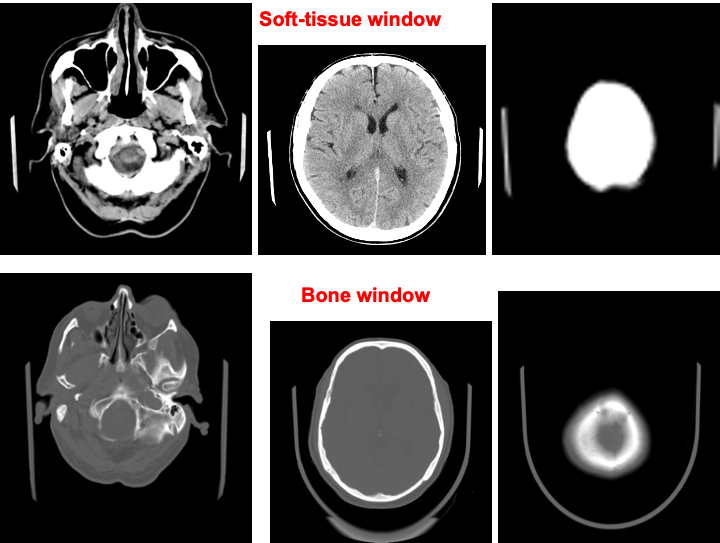

Two films are printed :

- The 1st is soft tissue.

- The second is bone window

Fractures of the skull base or vault should be looked for on bone window settings